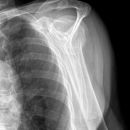

Schulterluxation